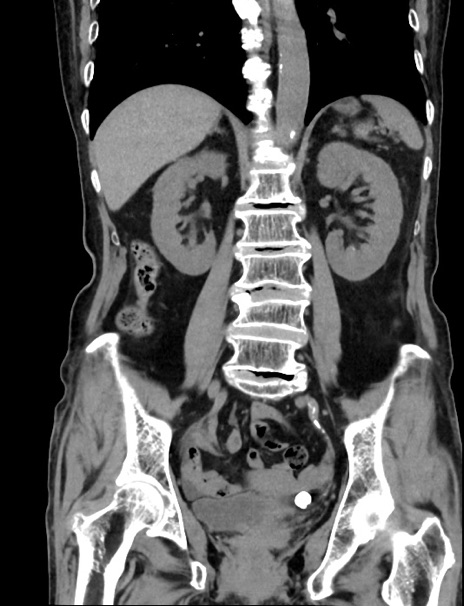

症例33(冠状断像)

【症例】70歳代 女性

【主訴】心窩部痛

【現病歴】延髄病変の精査・加療にて神経内科入院中。本日より心窩部痛あり。

【身体所見】右下腹部を中心に圧痛と反跳痛あり。

【データ】WBC 10900、CRP 0.02